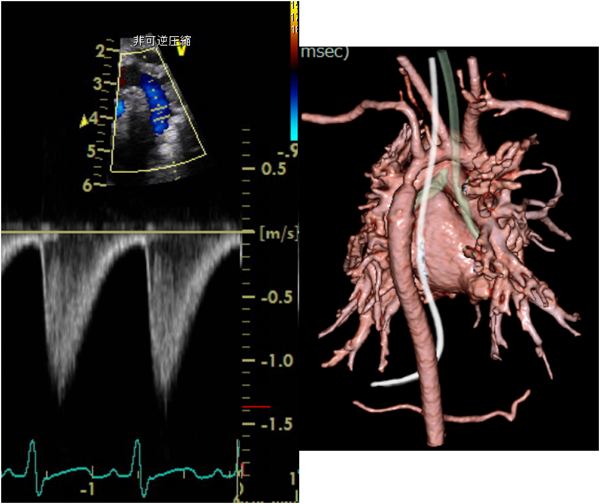

7) Trans-systolic murmur(Fig. 8

動脈の狭窄がある場合に聴取される.大動脈縮窄の血流速波形で示されるように収縮期から拡張にわたる雑音となる.

Pediatric Cardiology and Cardiac Surgery 32(2): 129-140 (2016)

Fig. 8 Doppler flow wave and computed tomography image of 23-day-old boy with coarctation of the aorta, ventricular septal defect, and patent ductus

This is a typical trans-systolic flow, and we can also hear a trans-systolic murmur at the back of the body in this patient. The ultrasonic Doppler flow wave pattern seems to be similar to a heart murmur pattern. Therefore, the ultrasonic Doppler flow wave pattern provides useful information about the heart murmur. When you conduct an echocardiography exam, please listen to the Doppler signal sound. It helps you to understand the heart murmur.